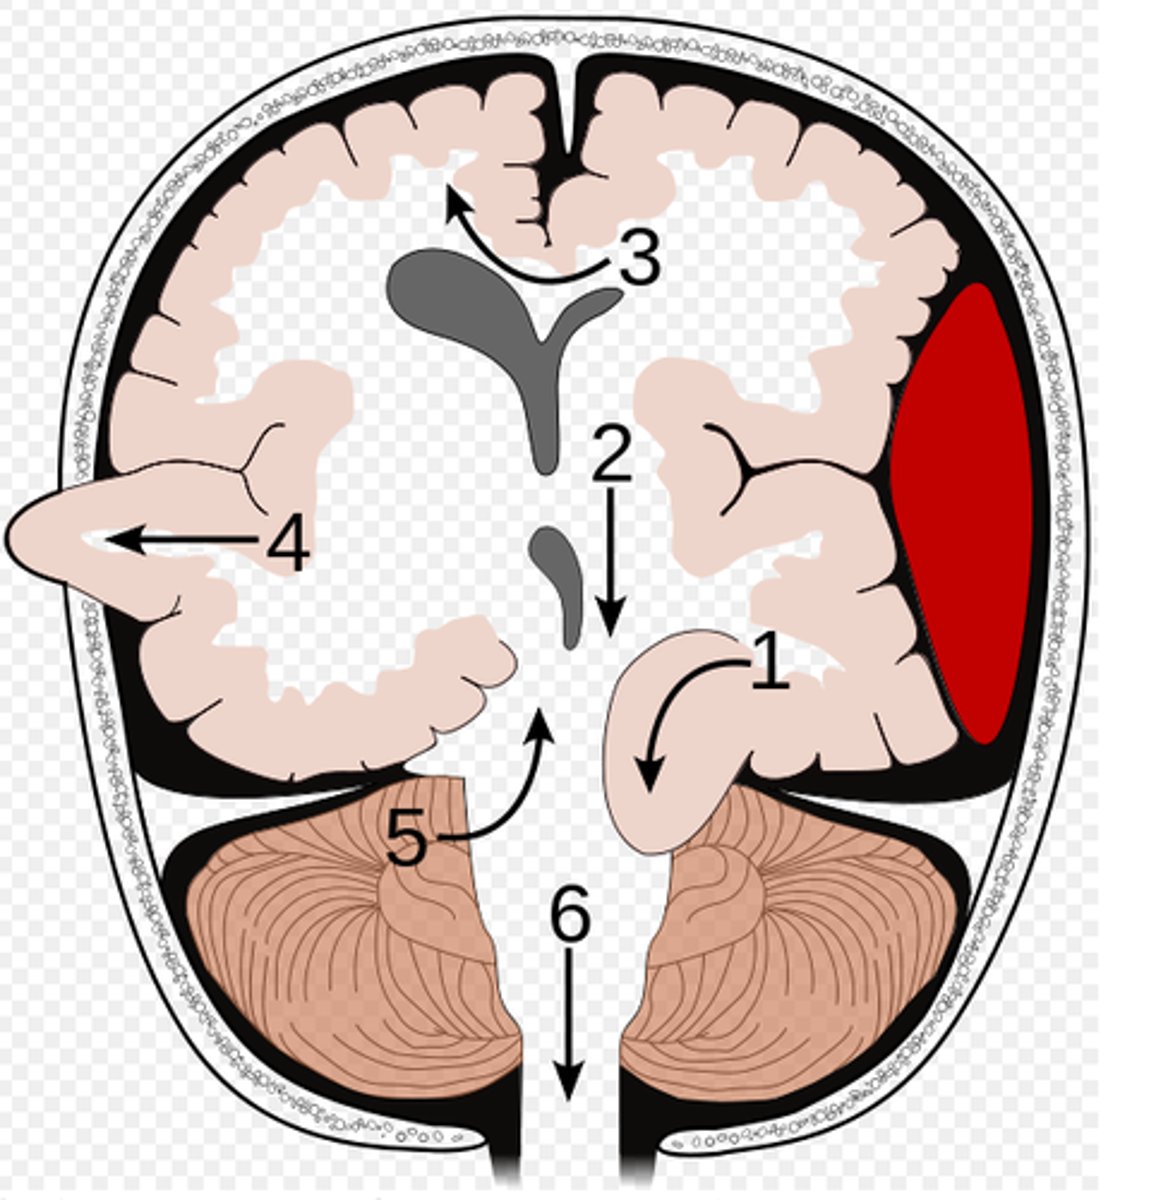

What is an uncal herniation?

most common.

unilateral lesions forces uncus of temporal lobe to displace and compress on the midbrain.

What is a central herniation?

Downward shift of cerebral hemisphere, compressing the brainstem

What is a cingulate herniation?

shift of brain tissue from one hemisphere to the other. Compress anterior cerebral artery.

Ischemic stroke may occur

What is a transcalvarian herniation?

brain begins to herniate outside of the skull. the brain will squeeze out of fractures, burr holes, or surgical incisions.

What is an upward herniation?

displacement of the cerebellum upward

What is a cerebellar Tonsillar herniation?

displacement of cerebellar tonsils downward this compressing the pons/medulla

s/s: alterations in resp. and cardiac functions- rapidly progressing to cardiac arrest, Headache and neck stiffness, reduced muscle tone